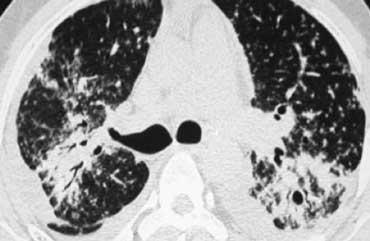

Đây là một trường hợp sarcoidosis phế nang.

Hãy cuộn qua các hình ảnh.

Hình ảnh trông giống như tăng tỷ trọng dạng kính mờ, nhưng khi quan sát kỹ hơn có thể nhận thấy rằng sự tăng tỷ trọng này là kết quả của nhiều nốt nhỏ tập hợp lại.

Cũng lưu ý hạch to rốn phổi.